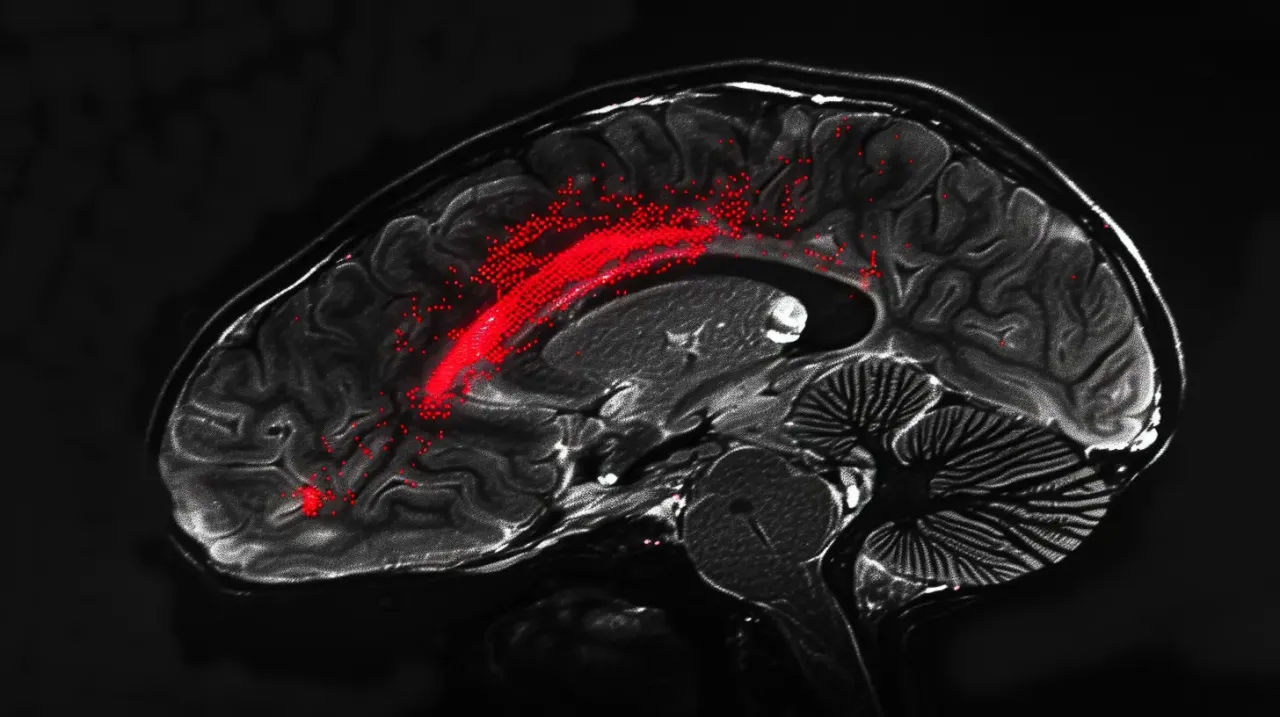

Wśród zalecanych procedur diagnostycznych znajdują się badania obrazowe, takie jak rezonans magnetyczny (MRI) oraz tomografia komputerowa (TK), które pozwalają na dokładną ocenę stanu mózgu. W zależności od wyników, lekarz może skierować pacjenta na dalsze badania lub zaproponować odpowiednie leczenie. Warto pamiętać, że szybka reakcja na pojawiające się objawy może uratować życie i poprawić rokowania na przyszłość.